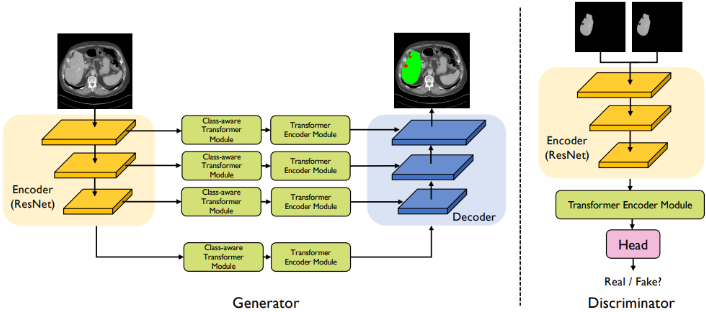

CASTformer

Paper: 《Class-Aware Generative Adversarial Transformers for Medical Image Segmentation》

Accepted by NeuraIPS 2022.

CASTformer 是 CNN + Transformer 组合而成的混合网络结构,通过整合多尺度金字塔结构以捕获丰富的全局空间信息和局部多尺度上下文信息。此外,进一步的应用生成对抗训练的策略用于提高分割性能,使基于 Transformer 的判别器能够捕获低级解剖特征和高级语义。